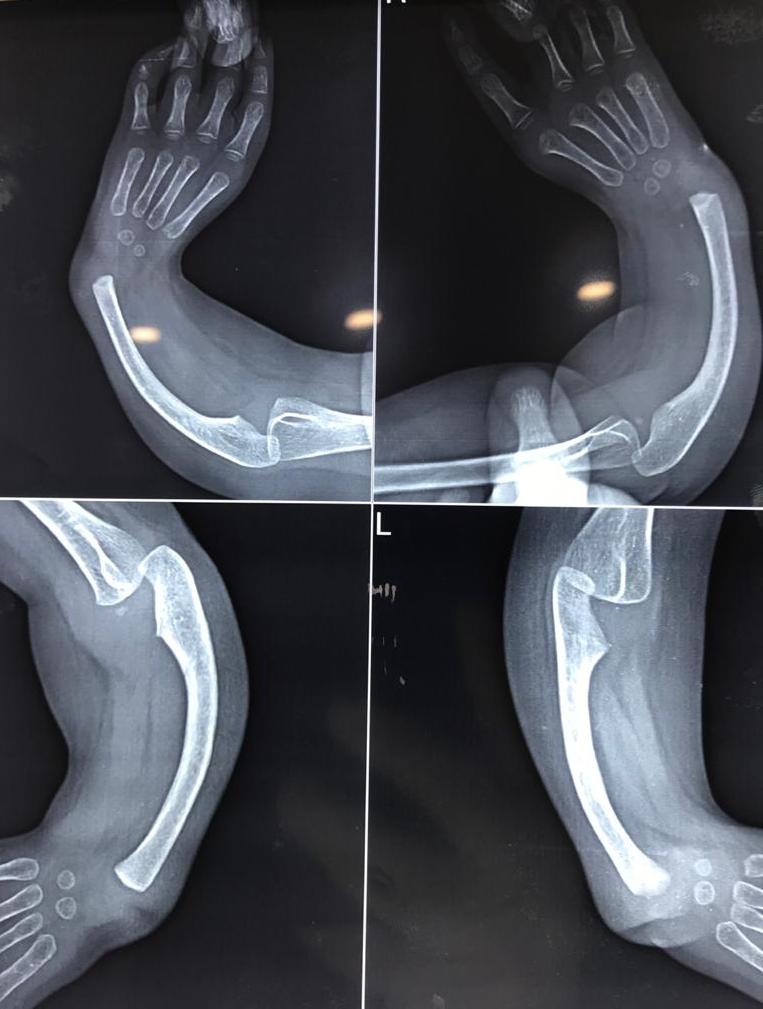

Bothbone Forearm Fracture

img2